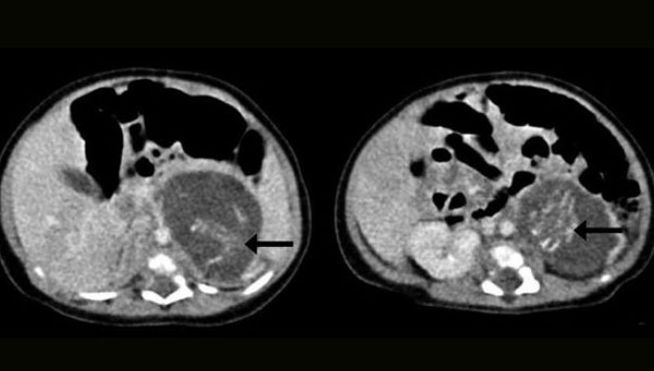

Si è trattato quindi di una gravidanza gemellare atipica, in cui parte delle cellule staminali di una blastocisti si localizzano tra le cellule di un embrione in formazione e procedono a una differenziazione autonoma.

Il fetus in fetu si caratterizza per un non normale sviluppo embrionale, per cui i tessuti che formano un feto crescono e si differenziano all’interno del corpo di un gemello normalmente sviluppato. Tale patologia dipende con tutta probabilità da una anomalia che avviene all’atto della fecondazione.